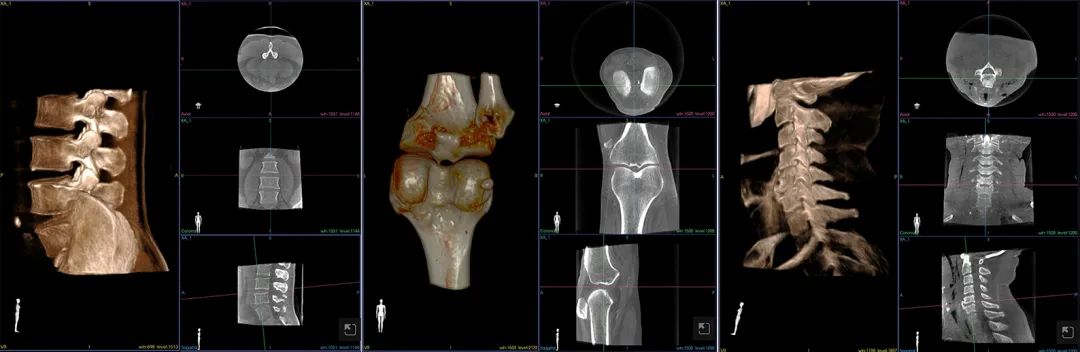

另外,劉新宇教授對(duì)歌銳術(shù)中CBCT也給予了高度評(píng)價(jià)。他表示,歌銳CBCT僅用12s~14s即可完成影像掃描及三維重建,節(jié)省了時(shí)間,圖像精度達(dá)0.16mm,滿足了外科精準(zhǔn)手術(shù)的需求,此外,偏心投照的設(shè)計(jì)十分人性化,為通道穿刺等臨床工作提供了便利。

專門開(kāi)發(fā)的“牛頓”3D高精度術(shù)中CT可獲得超高精度影像,是微創(chuàng)手術(shù)規(guī)劃和執(zhí)行的基礎(chǔ)